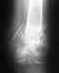

По этому снимку не очень хорошо видно, похоже, вовлечена суставная поверхность. Надо делать КТ. Возможно, что-то надо будет еще сделать, если форма суставной поверхности не восстановлена. А есть снимок до наложения аппарата?